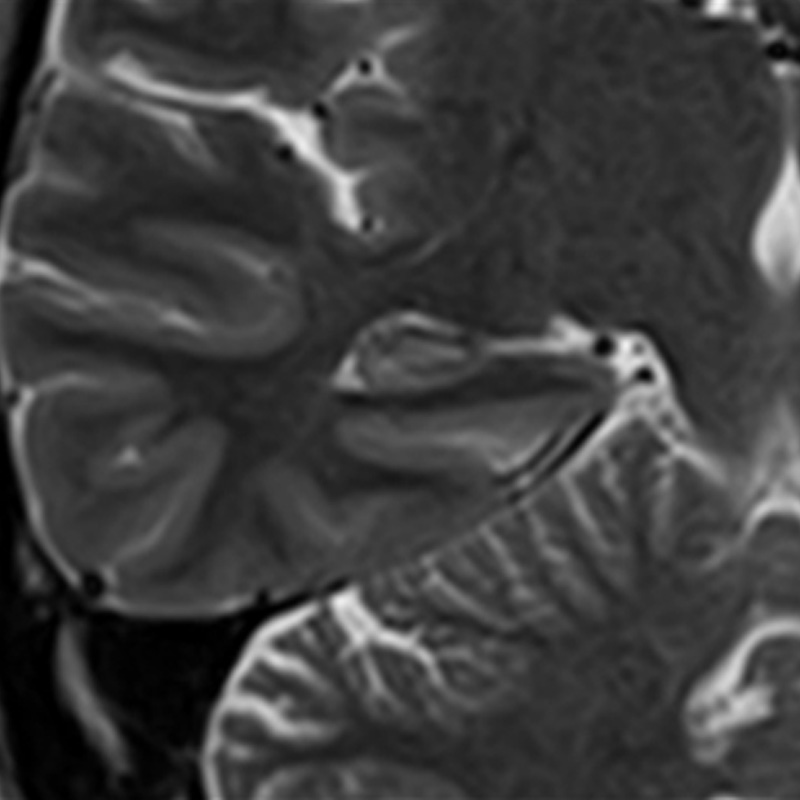

Cor T2w for hippocampus

Example of a high-resolution image of the hippocampus using Precise IQ Engine (PIQE). The original image is 256 matrix with low resolution and high signal-to-noise ratio (SNR).

Even though the scan time is reasonably short and the slice thickness is as thin as 2 mm, the image is clear and demonstrates good contrast.